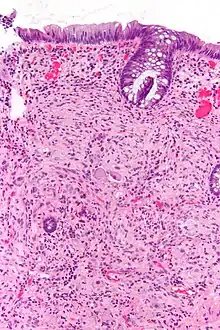

Pathology

Pathologically, ganglioneuromas are composed of ganglion cells, Schwann cells and fibrous tissue.[5] Ganglioneuromas are solid, firm tumours that typically are white when seen with the naked eye.

Renal ganglioneuroma -

Ganglioneuroma of the adrenal gland